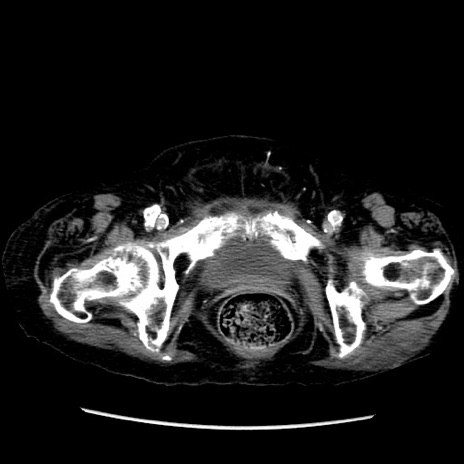

冠状断像